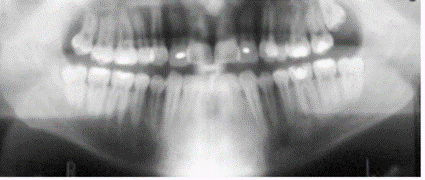

Note how narrow the incisors appear.